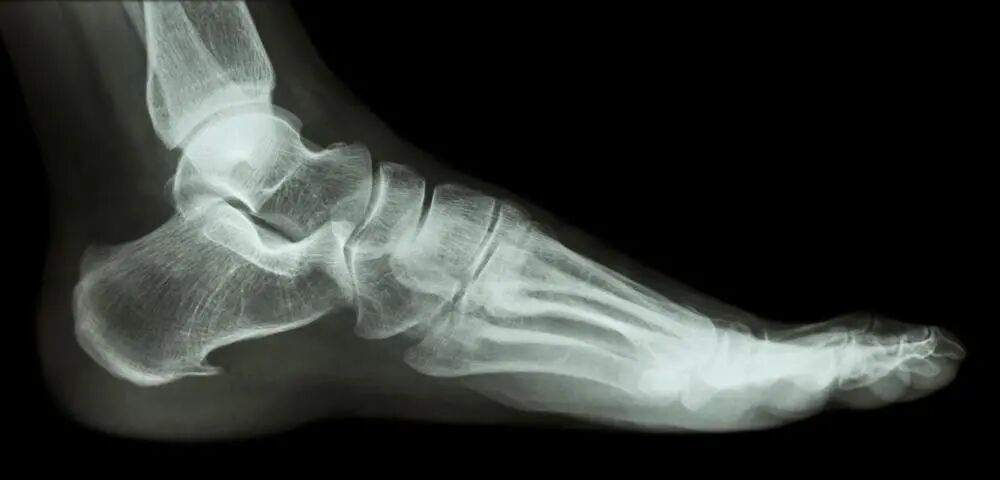

如果有所谓的跟骨骨刺,其位于第一肌肉层或者更深的固有肌层(如跖方肌)内,后者起自跟骨足底面。

应当认识到跟骨下骨刺,本质上其实是足底肌肉骨性化性肌炎的一部分,而不是跖筋膜,在无症状的个体中近 40% 都发现钙化,因此跟骨骨刺其实是不合理的称谓。

怀疑是足底筋膜炎引起疼痛的患者需要进行X线和MRI检查,以排除隐匿性骨性病变和肿瘤。足底筋膜炎在X线上无明显改变。

同位素骨扫描可以发现足底筋膜在内侧跟骨结节附着处摄取量增加,并可排除X线上难以显示的应力性骨折。